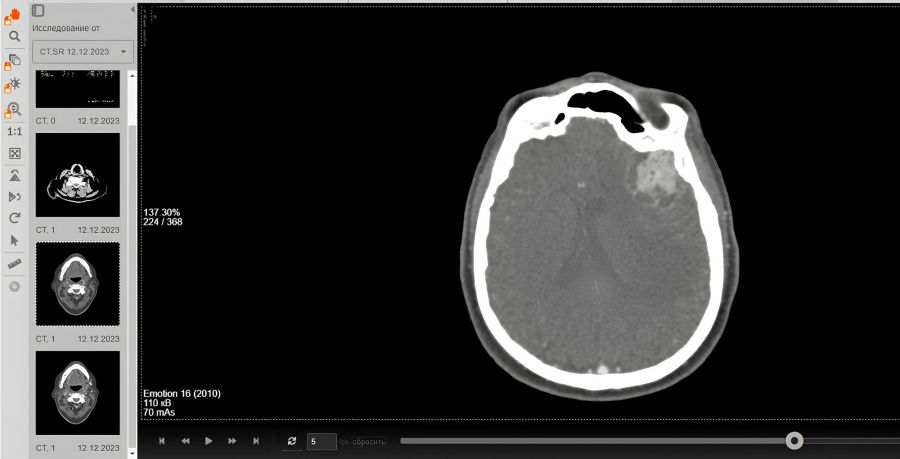

Пациентка поступила в больницу в тяжёлом состоянии: у неё отсутствовала речь. Томография позволила диагностировать отёк мозга и крупную, размером с грецкий орех, опухоль в зоне речевого центра коры головного мозга. В таком состоянии человек теряет способность говорить, но может понимать окружающих.